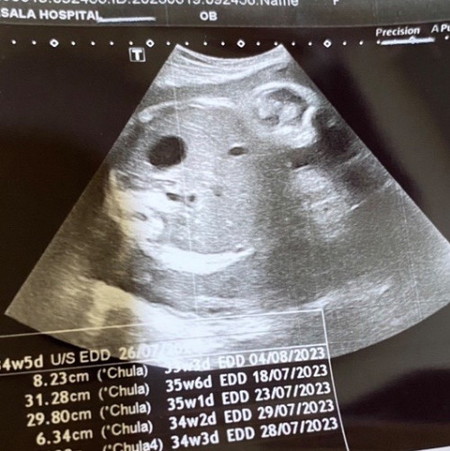

ในภาพพอจะเห็นเพศน้องมั้ยค่ะ 35 สัปดาห์ น้ำหนักน้องแค่ 2,222 เองค่ะ

ในภาพพอจะเห็นเพศน้องมั้ยค่ะ 35 สัปดาห์ค่ะ น้ำหนักน้อง 2,222 ค่ะ ของแม่ๆ อายุครรภ์35 สัปดาห์น้ำหนักเท่าไหร่กันบ้างค่ะ

ในรูปซาวน์เป็นพุงน้องนะคะแม่ ไม่เห็นเพศค่ะ ของเรา 34w น้องหนัก 2,160 หมอบอก ตามเกณฑ์ไม่เล็กไม่ใหญ่ 35w 2.2kg ก็น่าจะตามเกณฑ์นะคะ